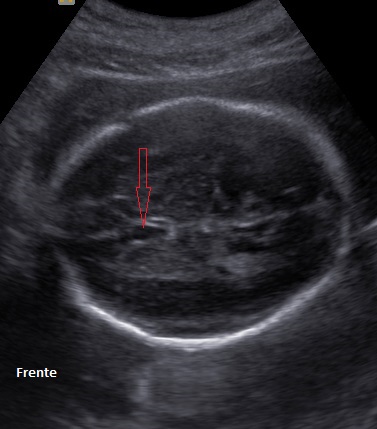

Cráneo

La determinación de la normalidad anatómica depende de la etapa del desarrollo en la que se pretende estudiar en contenido encefálico y del momento de aparición de las anomalías posibles; además, a diferencia de otros órganos cuya estructura madura es bastante estable y resistente a agresiones durante el embarazo, el contenido craneal puede verse afectado en cualquier etapa del embarazo, durante el nacimiento y en vida posnatal.